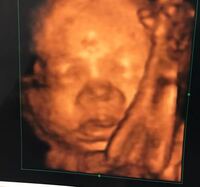

鼻 どうですか 23週の時の4dです 鼻低いでしょうか 2dで 妊活 教えて Goo

妊娠9ヶ月のエコー写真です 先日やっと顔がはっきりと見え主人とど Yahoo 知恵袋